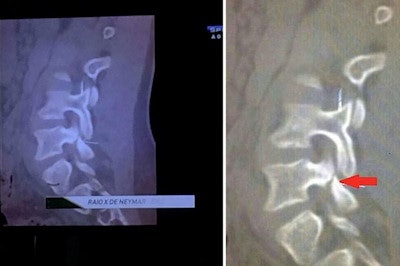

But controversy has been building within the medical community after Brazilian TV posted what it said was an "x-ray image" (actually a CT scan) of Neymar's injured vertebra over the weekend. The image purported to show the damage Neymar suffered in the incident, with some sources claiming that the star could have been paralyzed if he had been hit just slightly higher on the back.

This image has gained much attention after being shown on Brazilian TV, but its authenticity has been questioned.

This image has gained much attention after being shown on Brazilian TV, but its authenticity has been questioned.However, a number of imaging experts have criticized the image, pointing out that it does not show any acute damage to the L3 vertebra; instead, it seems to indicate damage to the L5 vertebra that's more consistent with a chronic condition -- a pathology that Neymar may have been playing with for some time.

Valassina also notes the image posted by Brazilian media does not denote an L3 fracture, but instead spondylolysis of the L5 vertebra: "an interruption of the posterior arch of the vertebra L5 likely ... nontraumatic." In fact, the radiological characteristics of the image seem to suggest an "old disease," Valassina notes.

A conversation on Reddit also noted that the scan did not appear to show an acute injury to the L3 vertebra, and instead seemed to indicate a chronic condition. "I thought the team doctor said the fracture was on a transverse process of the L3?" one participant noted. "The image does not ... show an acute fracture, and the defect shown is not on a transverse process."

Another Reddit participant notes the discrepancy, stating "The problem is that his defect has sclerotic margins, which means he's had it for a long time." Like Valassina, several forum participants suggested that the scan denotes spondylolysis, a defect in the pars interarticularis of the vertebral arch, which most often occurs in the L5 vertebra. The contact with Zuniga did not cause the injury, but could have aggravated it, several participants noted.